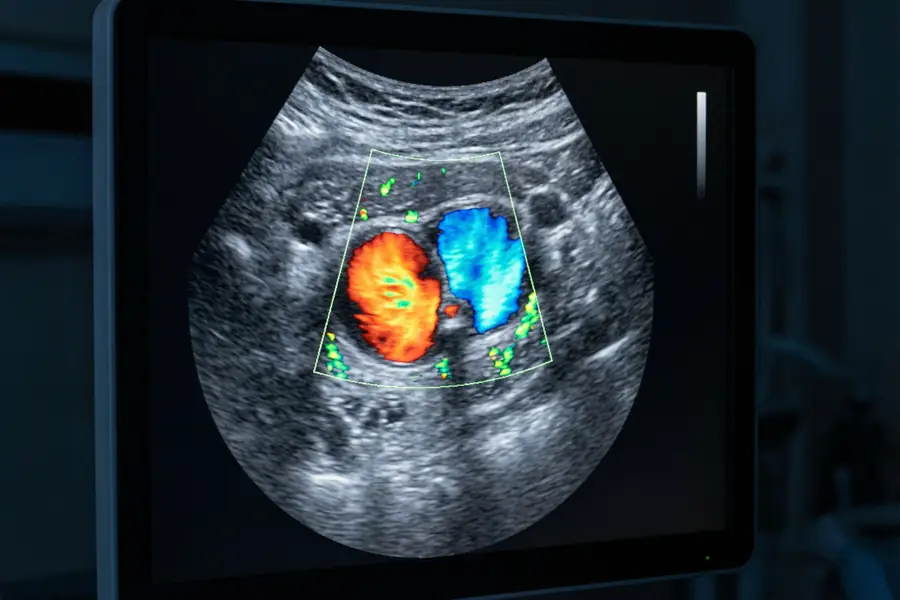

Colour Doppler ultrasound image showing femoral artery and vein during a DVT scan

Colour Doppler image: red = arterial flow, blue = venous flow. Absence of colour in the vein indicates thrombosis.

Colour Doppler maps the direction and velocity of blood flow within each vein. A normal vein shows spontaneous, phasic flow that augments with calf compression. Absent or reduced flow, combined with non-compressibility of the vein wall, indicates the presence of thrombus. The combination of B-mode and Doppler findings allows the sonographer to characterise whether a clot is acute or chronic.